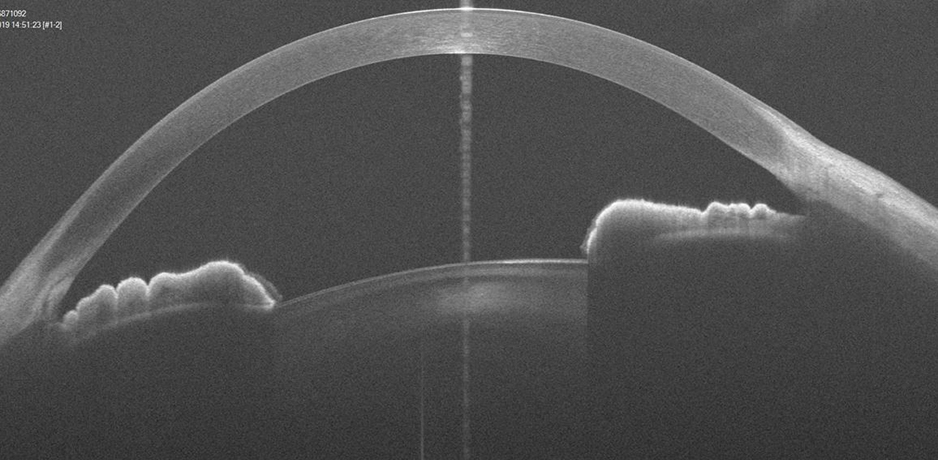

The ArcScan Insight® 100 is an intelligent anterior segment imaging system that uses very high frequency ultrasound technology. The ArcScan Insight® 100 device and software create a powerful platform that enables users to easily obtain stunning high resolution images in micron precision of the entire anterior segment, including areas that can not be imaged with optical technologies.

Precision imaging behind the iris for better ICL/IOL sizing.

Wide-angle cornea layer mapping for keratoconus screening and inlay evaluations.